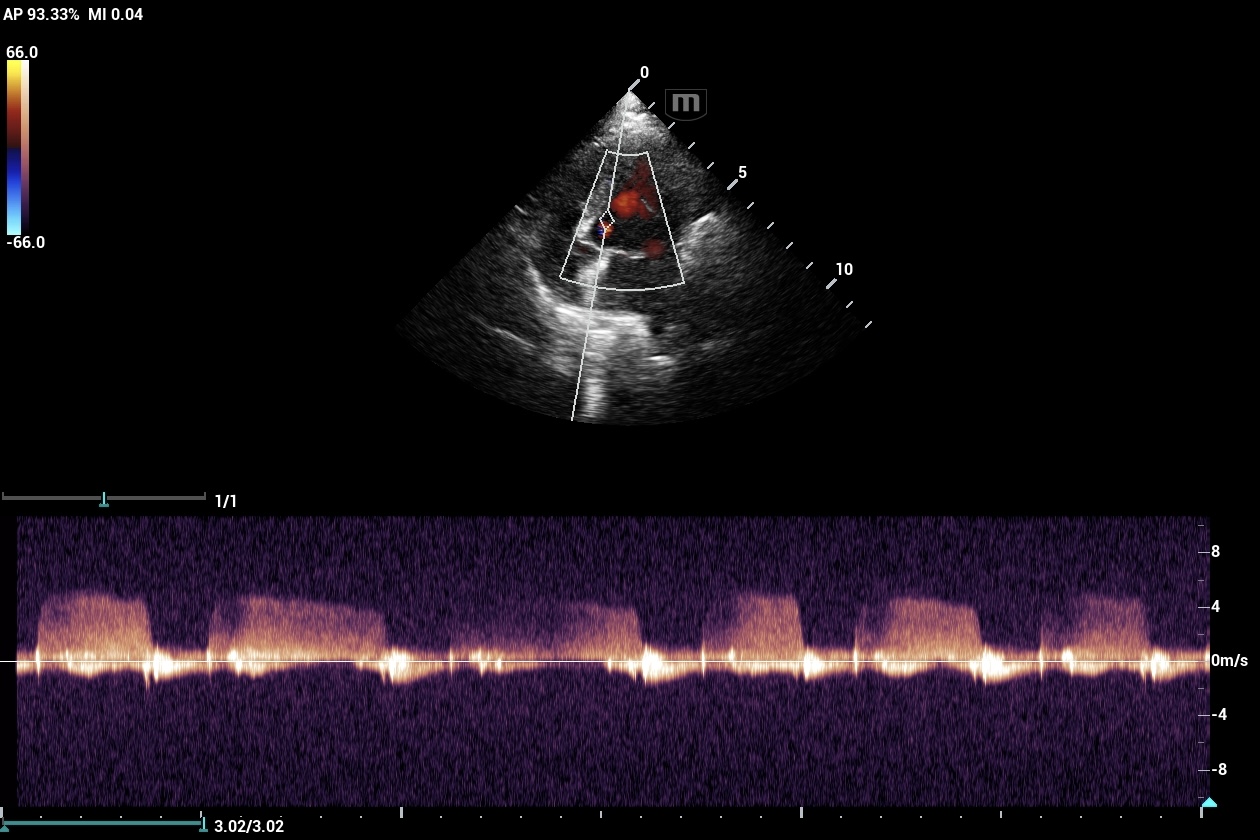

14Kg KCCS Dog; 3/6 murmur placed on Pimo after rads. Echo(3 wks later) revealed mild mod MV reg, TV reg and AO ins. PG – MV and TV=N. AO PG=N with plateau flow profile. Echo = stage B1 MVD, BP= N.Dog was 5 lbs ovweight. C index adj. to 11.7Kg= N.

Sonographically B1 and B2 I go to the atrial septum and ensure its deviated toward the right atrium and not in line wiht the IVS. Your echo the AS is in line wiht the UVS and not deviated and there fore no LAE in this case. I use the LA max measurement and ensure there is a solid MR jet and not a small one. I dont have rads available in many of my interps so from the sonographer perspective this tends to work well. If pimo other tx has been given and the LA is normal and you dont know if the LA is normal because of tx or its normal because it didnt need it, then I go to the level of MR because the MR has to have. alarge regurguitant flow to eventually cause LA enlargement. Then of course checking rads to see if they misinterpreted the rads as LAE which happens a lot. Otherwise stop the pimo for a week and rescan and see what the lA is doing. If just B2 they should be good wihtout tx for a week to find out if the tx direction is correct. Your case looks very B1. Hope this helps

No LAE on rad, VLAS =1.74,VHS = high normal for a KCCS 11.78. Echo was normal. The heart had a few minor “leaks” , dog was being treated and the owner felt the dogs activity and energy improved on meds. Wasn’t sure if increased quality noted in a B1 dog put on meds would warrant continuation or one should always follow protocol. It’s possible owner subjectivity could be biased too.Will stop meds and observe response.